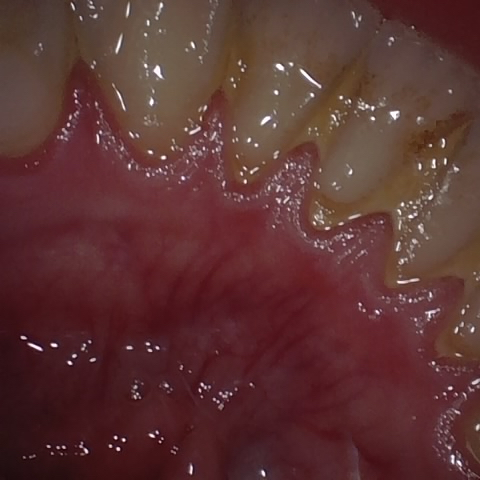

Annotated as "Bad"